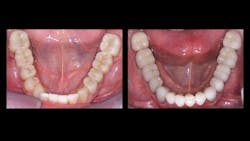

Crowns seat easily because of laboratory spacing of virtual dies. The intaglio surfaces of zirconia crowns are smooth, because the scanned impressions and computer spacing have eliminated the diamond scratches and other irregularities on the preps (figures 1 and 2). Because of this spacing, zirconia crowns seat without resistance. Dentists and patients are pleased when crowns seat easily, but the preps should be slightly deeper.

Open margins of milled zirconia crowns: Scanners space the external of crown preps a significant amount (note figure 1). This spacing is inadvertently extended to the margins, making the margins open more than previous cast-gold alloy or PFM crowns. In my opinion, it is mandatory to use cariostatic cements to provide reduction or elimination of subsequent caries on the crown margins. Good choices are resin-modified glass ionomers (3M RelyX Luting or GC FujiCEM Evolve)—not resin cements, which shrink on setting and do not have cariostatic properties. In high-caries patients, I suggest conventional glass ionomer cements such as GC Fuji I or 3M Ketac Cem.